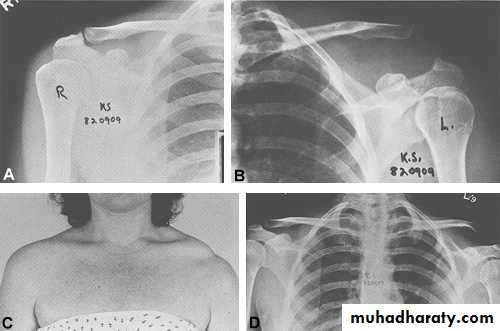

Traction in adduction then IRAcromioclavicular joint injury

Mechanism

Fall on the shoulder with arm adducted

Types

I : sprain of the AC ligament

II : subluxation

III : dislocation

XR

AP view

AP stress view

Rx

I & II : arm sling exercise

III : if pt is young or demanding occupation repair of the CC ligament + CC screw